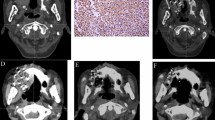

All patients underwent local infiltration anesthesia and intercostal nerve block. Then, depending on preoperative and intraoperative planning, RISI (with or without the assistance of a three-dimensional printed template) was performed under CT. The seeds spacing referenced the preoperative planning design to within 0.5–1.0 cm. Finally, we observed the actual distribution of seeds and, if necessary, supplemented seeds in real time. Operation processes are shown in Fig. 1. The technical insertion of radiation seed implants followed the expert consensus about radioactive seeds permanent interstitial brachytherapy1.